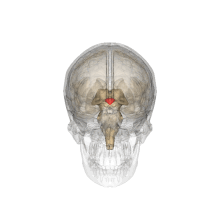

Der Hypothalamus (griech. ὑπό hypo „unter“ und θάλαμος thalamós „Zimmer, Kammer“) ist ein Abschnitt des Zwischenhirns (Diencephalon) im Bereich der Sehnervenkreuzung (Chiasma opticum). Medial wird der Hypothalamus vom dritten Ventrikel, kranial vom Thalamus begrenzt. Das Infundibulum, der sogenannte Hypophysenstiel, verbindet den Hypothalamus mit der Hypophyse, deren Hinterlappen noch als Teil des Hypothalamus bezeichnet wird. Der Hypothalamus bildet Effektorhormone, Releasing- und Inhibiting-Hormone, verschiedene Neuropeptide und Dopamin. Er steuert damit die vegetativen Funktionen des Körpers.